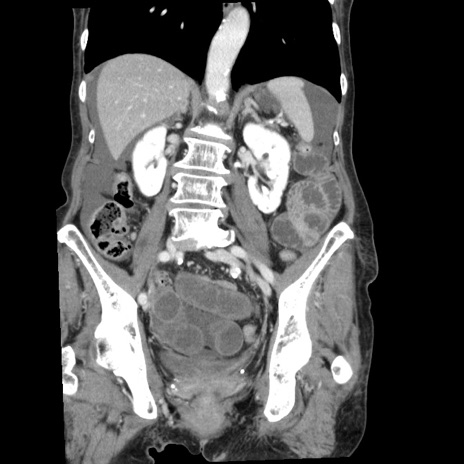

症例1(冠状断像)

【症例】80歳代女性

【主訴】腹痛

【現病歴】8時間前から腹痛あり来院。

【既往歴】糖尿病、脂質異常症、子宮体癌にて子宮全摘術

【身体所見】意識清明・会話良好だが腹痛で苦悶様、全腹部にわたって反跳痛と圧痛あり

【データ】WBC 13600、CRP 0.14、LDH 224、CK 90